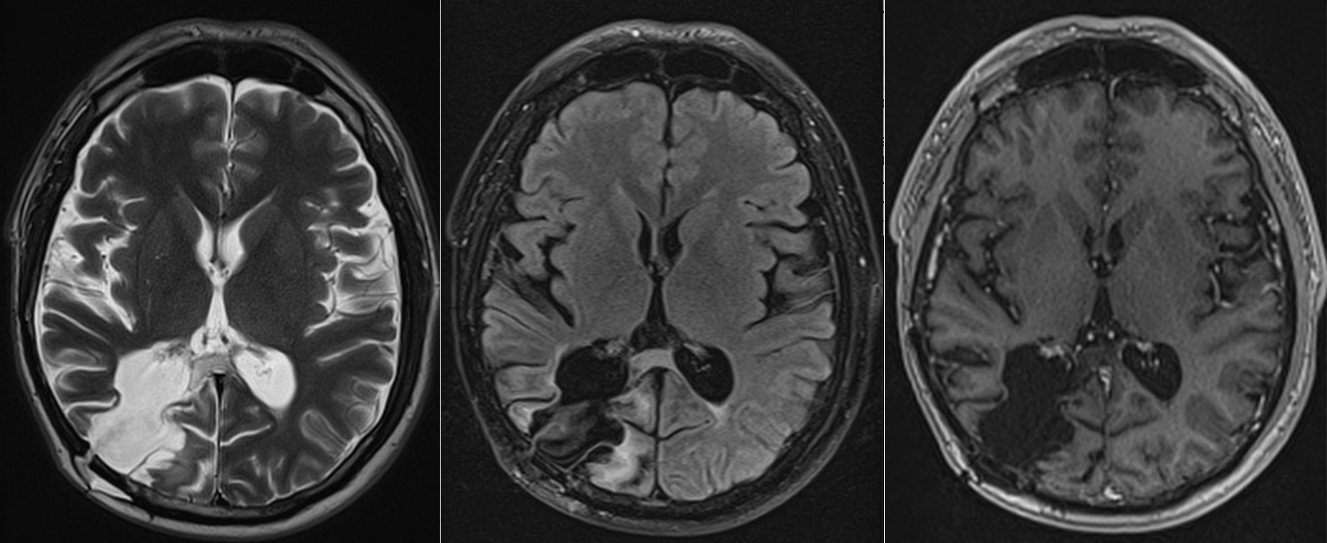

Investigația prin RMN cerebral a clarificat situația: exista o tumoră cerebrală situată în regiunea occipito-temporală dreaptă, o zonă a creierului implicată în procesarea informației vizuale și în recunoașterea fețelor.

Operația a decurs în condiții bune, iar tumora a fost rezecată într-o proporție foarte mare. Analiza microscopică a confirmat diagnosticul de astrocitom anaplazic (grad III) – o tumoră glială cu potențial agresiv.